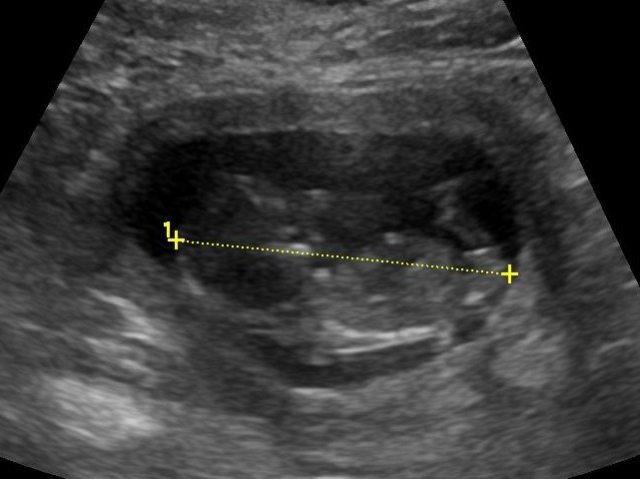

I have a few friends who love this forum and suggested I post my 12w6d scan pics to see if anyone can take a guess as to bub's gender.

I am currently 18w and our scan is on Thursday. Sorry, the photo isn't that great, I am not sure if you will even be able to see anything!